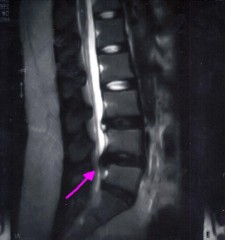

今日2ヶ月半ぶりのMRIを撮ってきた。

よくなってなかった。

むしろ、悪い方向に・・・

飛び出したヤツが、白くなっている=固まっていきよる

って言われた・・・・